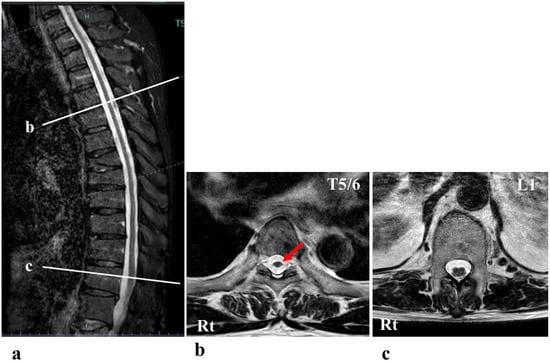

A 68-year-old man presented with progressive walking difficulties, which progressed to spastic paraplegia that began to worsen around the age of 40 years (Figure 1). This condition resulted from a high-tension electrical injury sustained at 22 years of age. He was struck by lightning while trekking in the Northern Japanese Alps. The lightning entered his body through the head and neck areas and exited through the lower extremities. Immediately after the injury, the patient became completely paralyzed. Two weeks post-injury, the patient began to recover gradually, and by 1 month post-injury, he was able to walk with a single T-cane. At 1 year post-injury, the patient regained the ability to walk without a cane, and this relatively stable condition persisted for more than 30 years. However, around the age of 40 years, his gait disturbance progressively worsened, requiring the use of a T-cane for mobility. The gait disturbance continued to deteriorate, and around the age of 63 years, the patient required double crutches for walking. At the age of 68 years, 46 years after the initial injury, the patient was admitted to our institution with a documented history of severe and worsening spastic paraplegia, prompting the initiation of HAL gait training. At the time of admission, his physical examination revealed that activities of daily living were substantially impaired because of severe spasticity in both lower limbs. He could only manage to stand up from his wheelchair with considerable support. While the patient was able to walk short distances using two crutches, his gait was unsteady and awkward. Prior to HAL training, the patient’s physical evaluation revealed a neurological level of injury of T10. According to the American Spinal Cord Injury Association impairment scale (AIS), the patient was classified as grade D [16]. The motor score, as per the International Standards for Neurological and Functional Classification of Spinal Cord Injury (ISNCSCI), was 76 points (right: 37 points; left: 39 points). The sensory score was 108 points, derived from both light touch and pinprick tests (right: 52 points; left: 56 points) [16,17]. The patient’s deep tendon reflexes were hyperactive in the lower extremities. Furthermore, his Walking Index for Spinal Cord Injury (WISCI) II score was 11 points [18,19]. His functional independence measure (FIM) motor score was 78 points [20]. Magnetic resonance imaging (MRI) showed that his thoracic spinal cord was slightly atrophic (Figure 2). Notably, there was no evidence of spinal cord compression or abnormal signal intensity within the spinal cord. Despite these findings, the patient reported a substantial progression of walking difficulties and challenges with daily activities over the past 20 years, and this was attributed to worsening spastic paralysis in the lower limbs. Previous reports suggest that there is no specific imaging modality to reliably diagnose SCI caused by electrical trauma as imaging findings are often unremarkable [21]. In cases where SCI symptoms are present, MRI and other imaging test results typically appear normal. Consequently, the diagnosis of neurological injury in such cases relies heavily on clinical findings and the progression of symptoms rather than imaging results [21]. Moreover, regarding the differential diagnosis in this case, the possibility of disuse atrophy was ruled out owing to the lack of clear muscle atrophy and the fact that spasticity in the lower limbs had intensified [22].

Figure 2.

Mid-sagittal section (a) and axial sections at the T5/6 level (b) and L1 level (c) of the T2-weighted magnetic resonance image showed that his thoracic spinal cord was slightly atrophic (arrow in (b)).